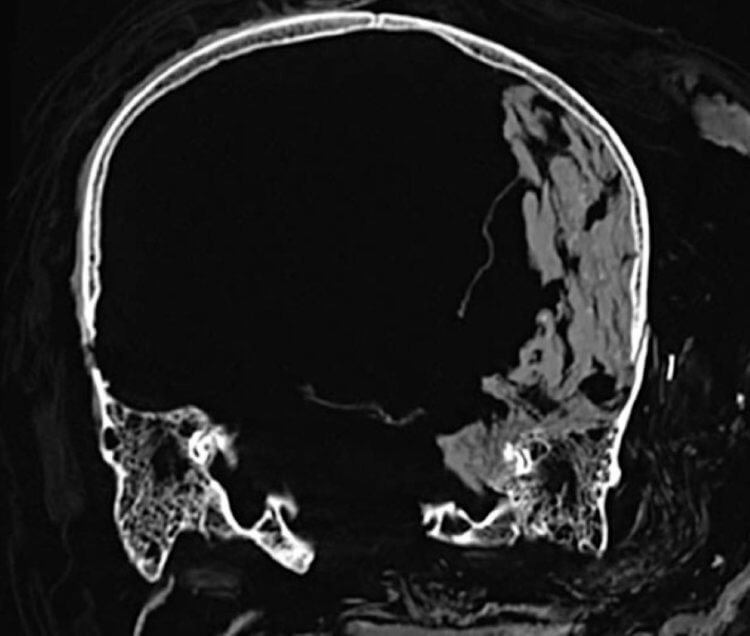

Томография головы фараона Секененра Таа II. На нем видно, что головной мозг смещен в одну сторону черепа

Тело фараона сохранилось очень плохо, исходя из чего исследователи сделали вывод, что между его смертью и бальзамированием прошло некоторое время. Сразу же после смерти он лежал на левом боку, о чем свидетельствует смещенный в левую сторону черепа головной мозг. Так как смерть фараона произошла за пределами его дома, перед бальзамированием его перетащили в город. Само бальзамирование происходило очень аккуратно, но почему его люди не извлекли головной мозг — неизвестно.